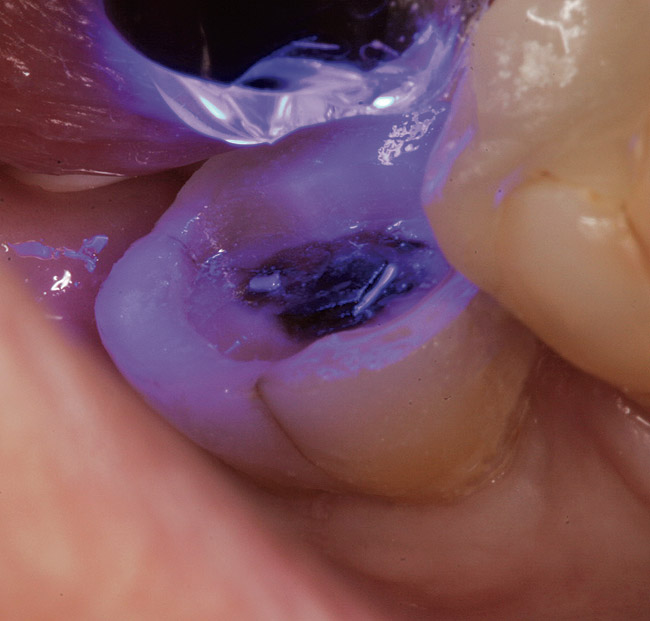

Figure 4  Application of a self-etching adhesive immediately after completion of tooth preparation.

Figure 4

A 70-year-old patient presented with symptoms of a cracked tooth scenario, with intermittent pain upon chewing and thermal sensitivity. The diagnosis was supported through various tests, which determined the lower right second molar had an incomplete fracture that extended from the distal marginal ridge to the mesial marginal ridge. After treatment options were presented, an all-ceramic restoration was decided upon. The tooth was prepared for a nonretentive, adhesively retained all-ceramic restoration ("table top" preparation) (Figure 2 and Figure 3). After the preparation was completed a mild self-etching adhesive was applied to the dentin according to the manufacturer's instruction (Figure 4). There was little concern, if any, of the adhesive reaching the band of exposed enamel. The adhesive was light-polymerized for 5 seconds to secure the layer to the dentin (Figure 5). To eliminate the oxygen-inhibited layer a water-soluble gel was applied to the adhesive and further light-polymerization was completed (Figure 6 and Figure 7). For direct digital scanning cases in which a powdering technique is employed for image capture, it may be more difficult to remove the powder after scanning if the oxygen-inhibited layer is still present.